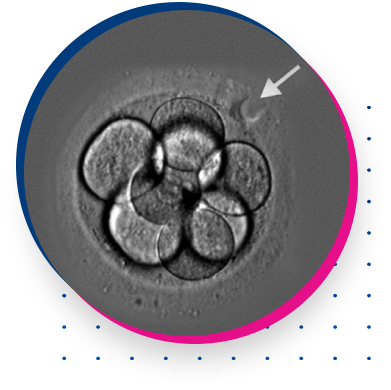

ASSISTED HATCHING